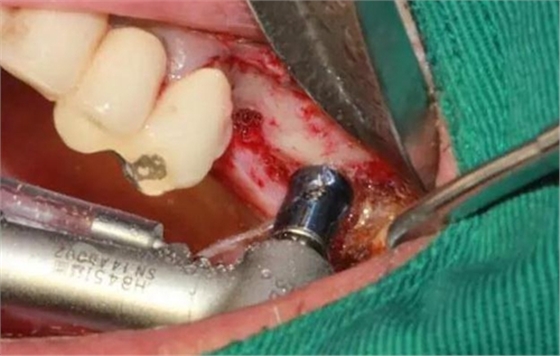

MASAL工具內(nèi)提升永磁鉆--這就是本病例改良開窗的關(guān)鍵

安全地在上頜竇外壁鉆一個洞

分離洞邊緣膜

CAS水壓剝離頰側(cè)竇膜(安全省事)

開窗永磁鉆

取下骨片可以看到,膜已經(jīng)剝離

擴大剝離面積